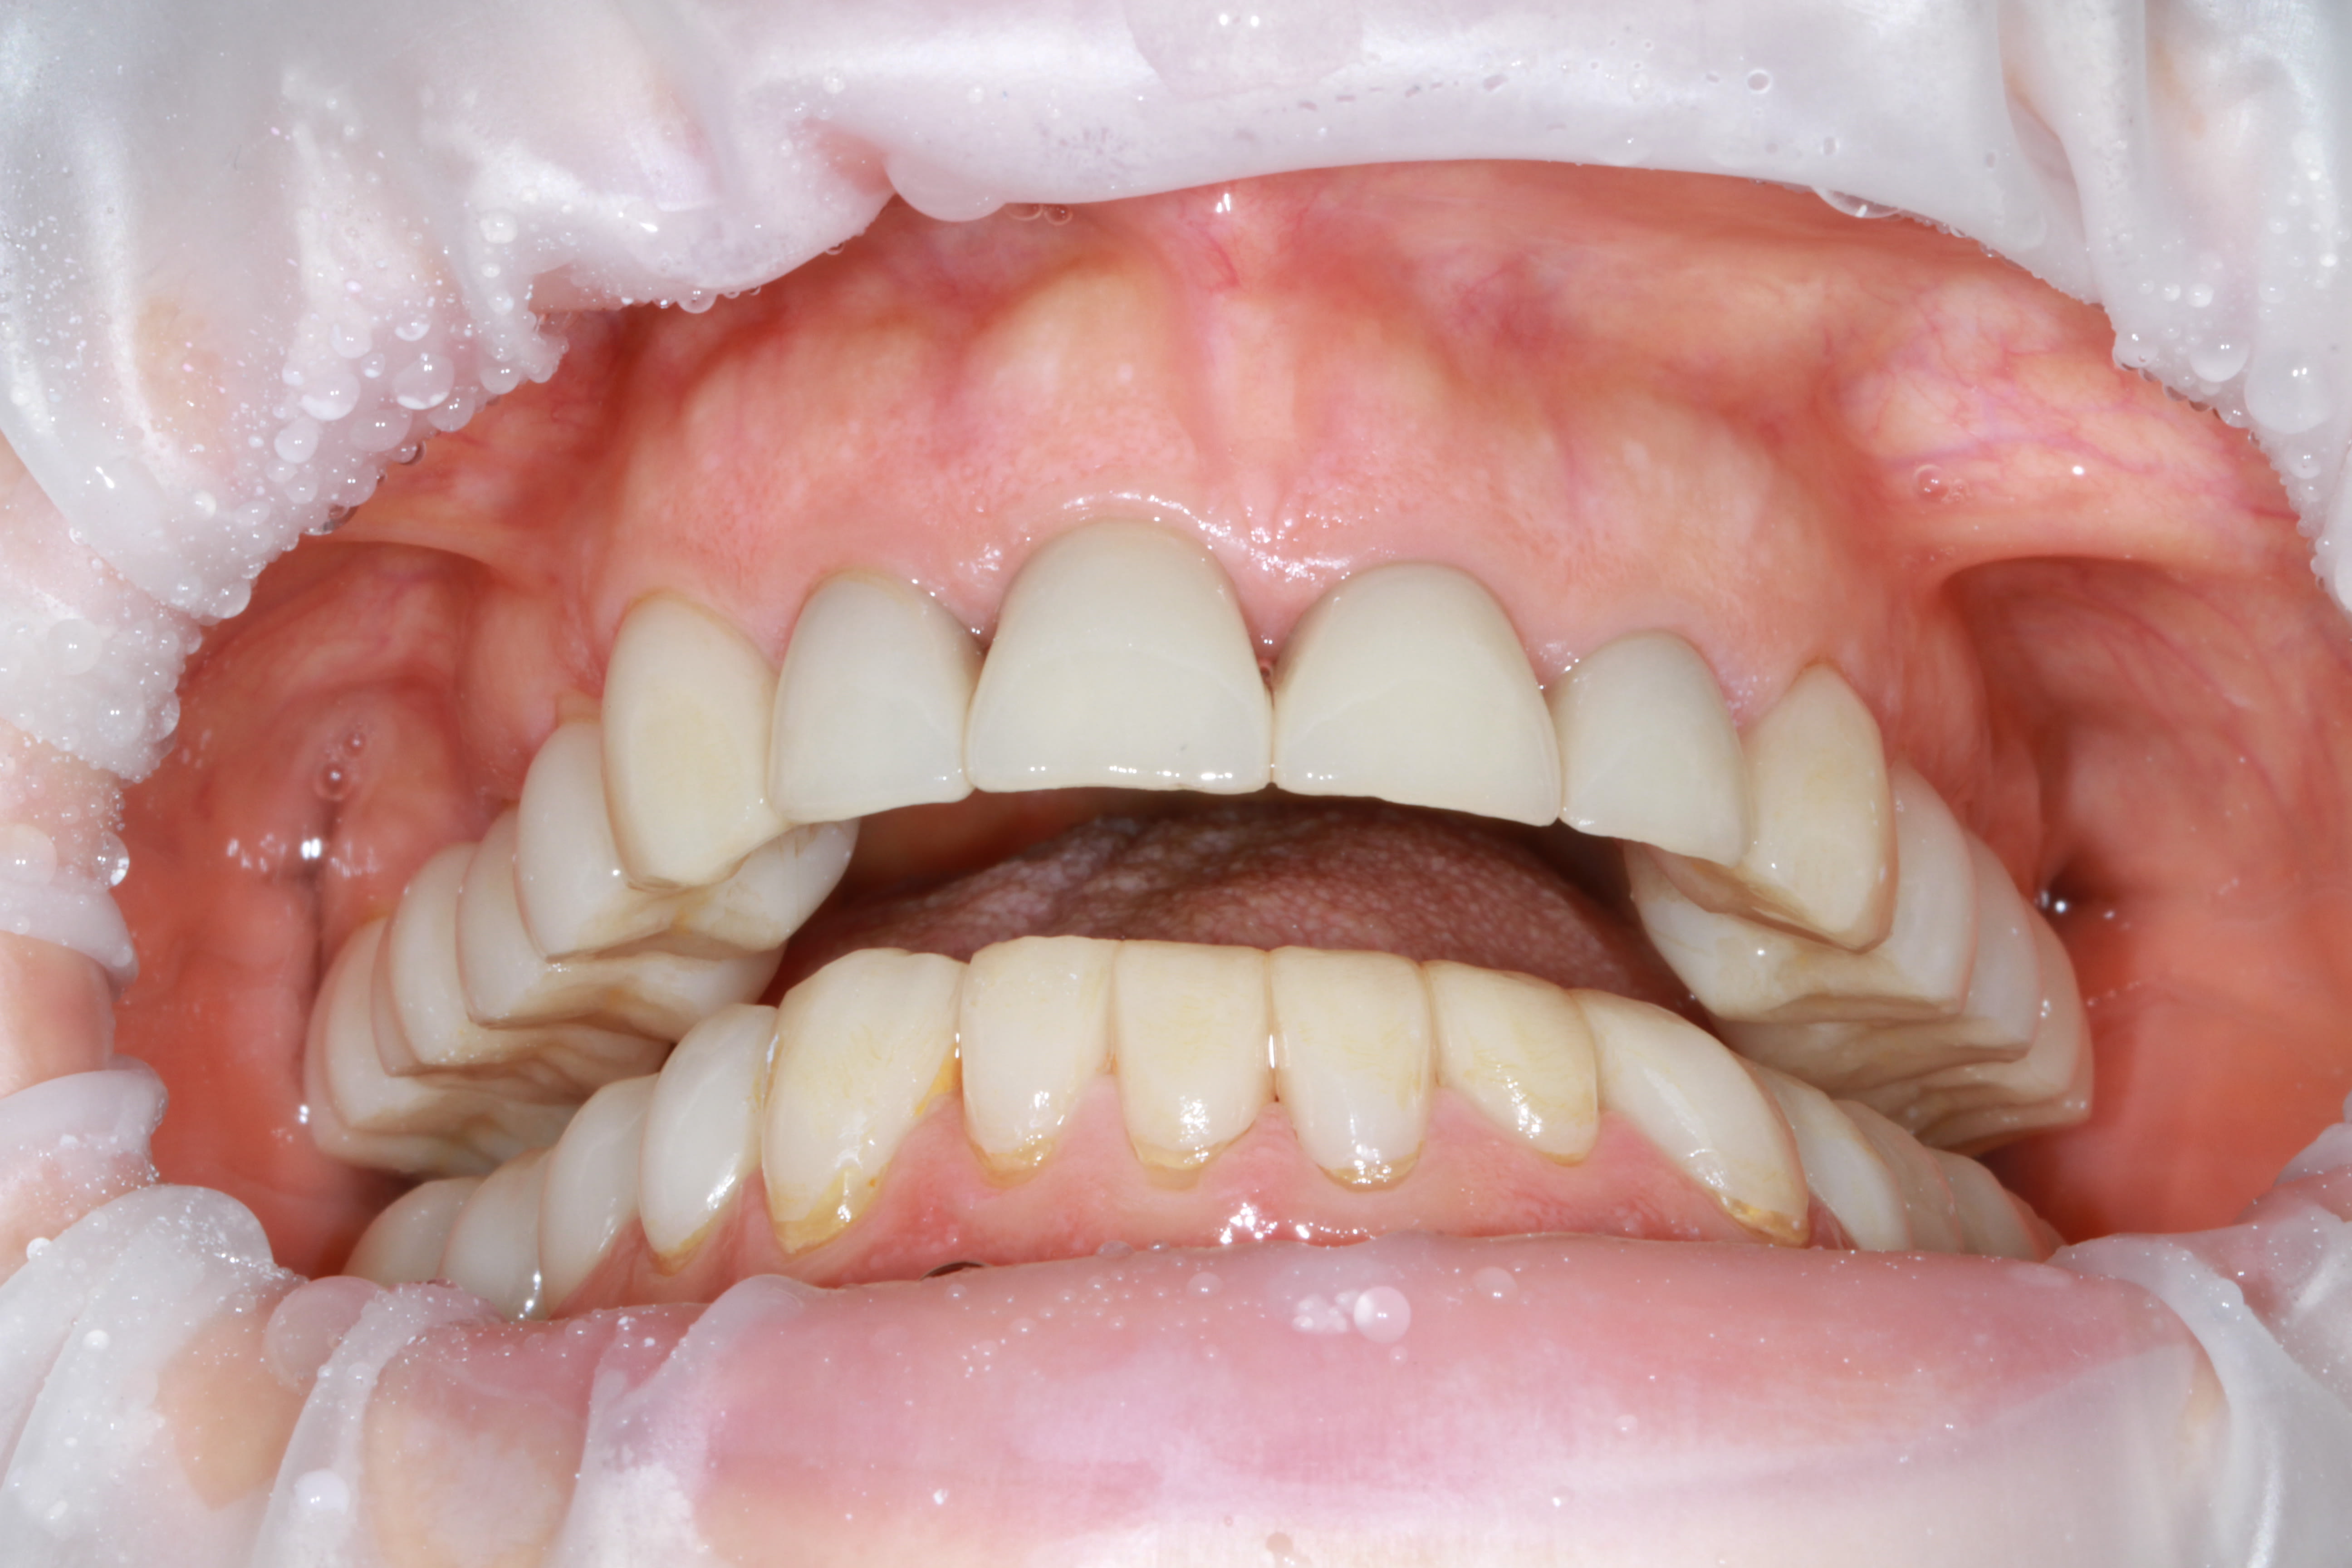

Chouette journée, toujours aussi bon l'ami....sauf en cadrage photo ;-) changes rien.

Ma p'tite B.A. CMU de l'été. On en a chier mais dans la joie et la bonne humeur et ni le gamin, ni moi ne regrettons l'aventure

On reste dans le cahier des charges du panier CMU, et non y'a presque plus rien de vital, et pour certaines il a fallu faire de l'élongation et de la reprise endo gratis. C'est tout IC et CCM scellé à l'ancienne.

Et l'organisation c'est simple: mois d'Aout, fait 40° à l'ombre, pas un chat à l'horizon, donc il a bien voulu me tenir compagnie scotché au fauteuil toute la journée 1X par semaine.... le pauvre, il en a chier